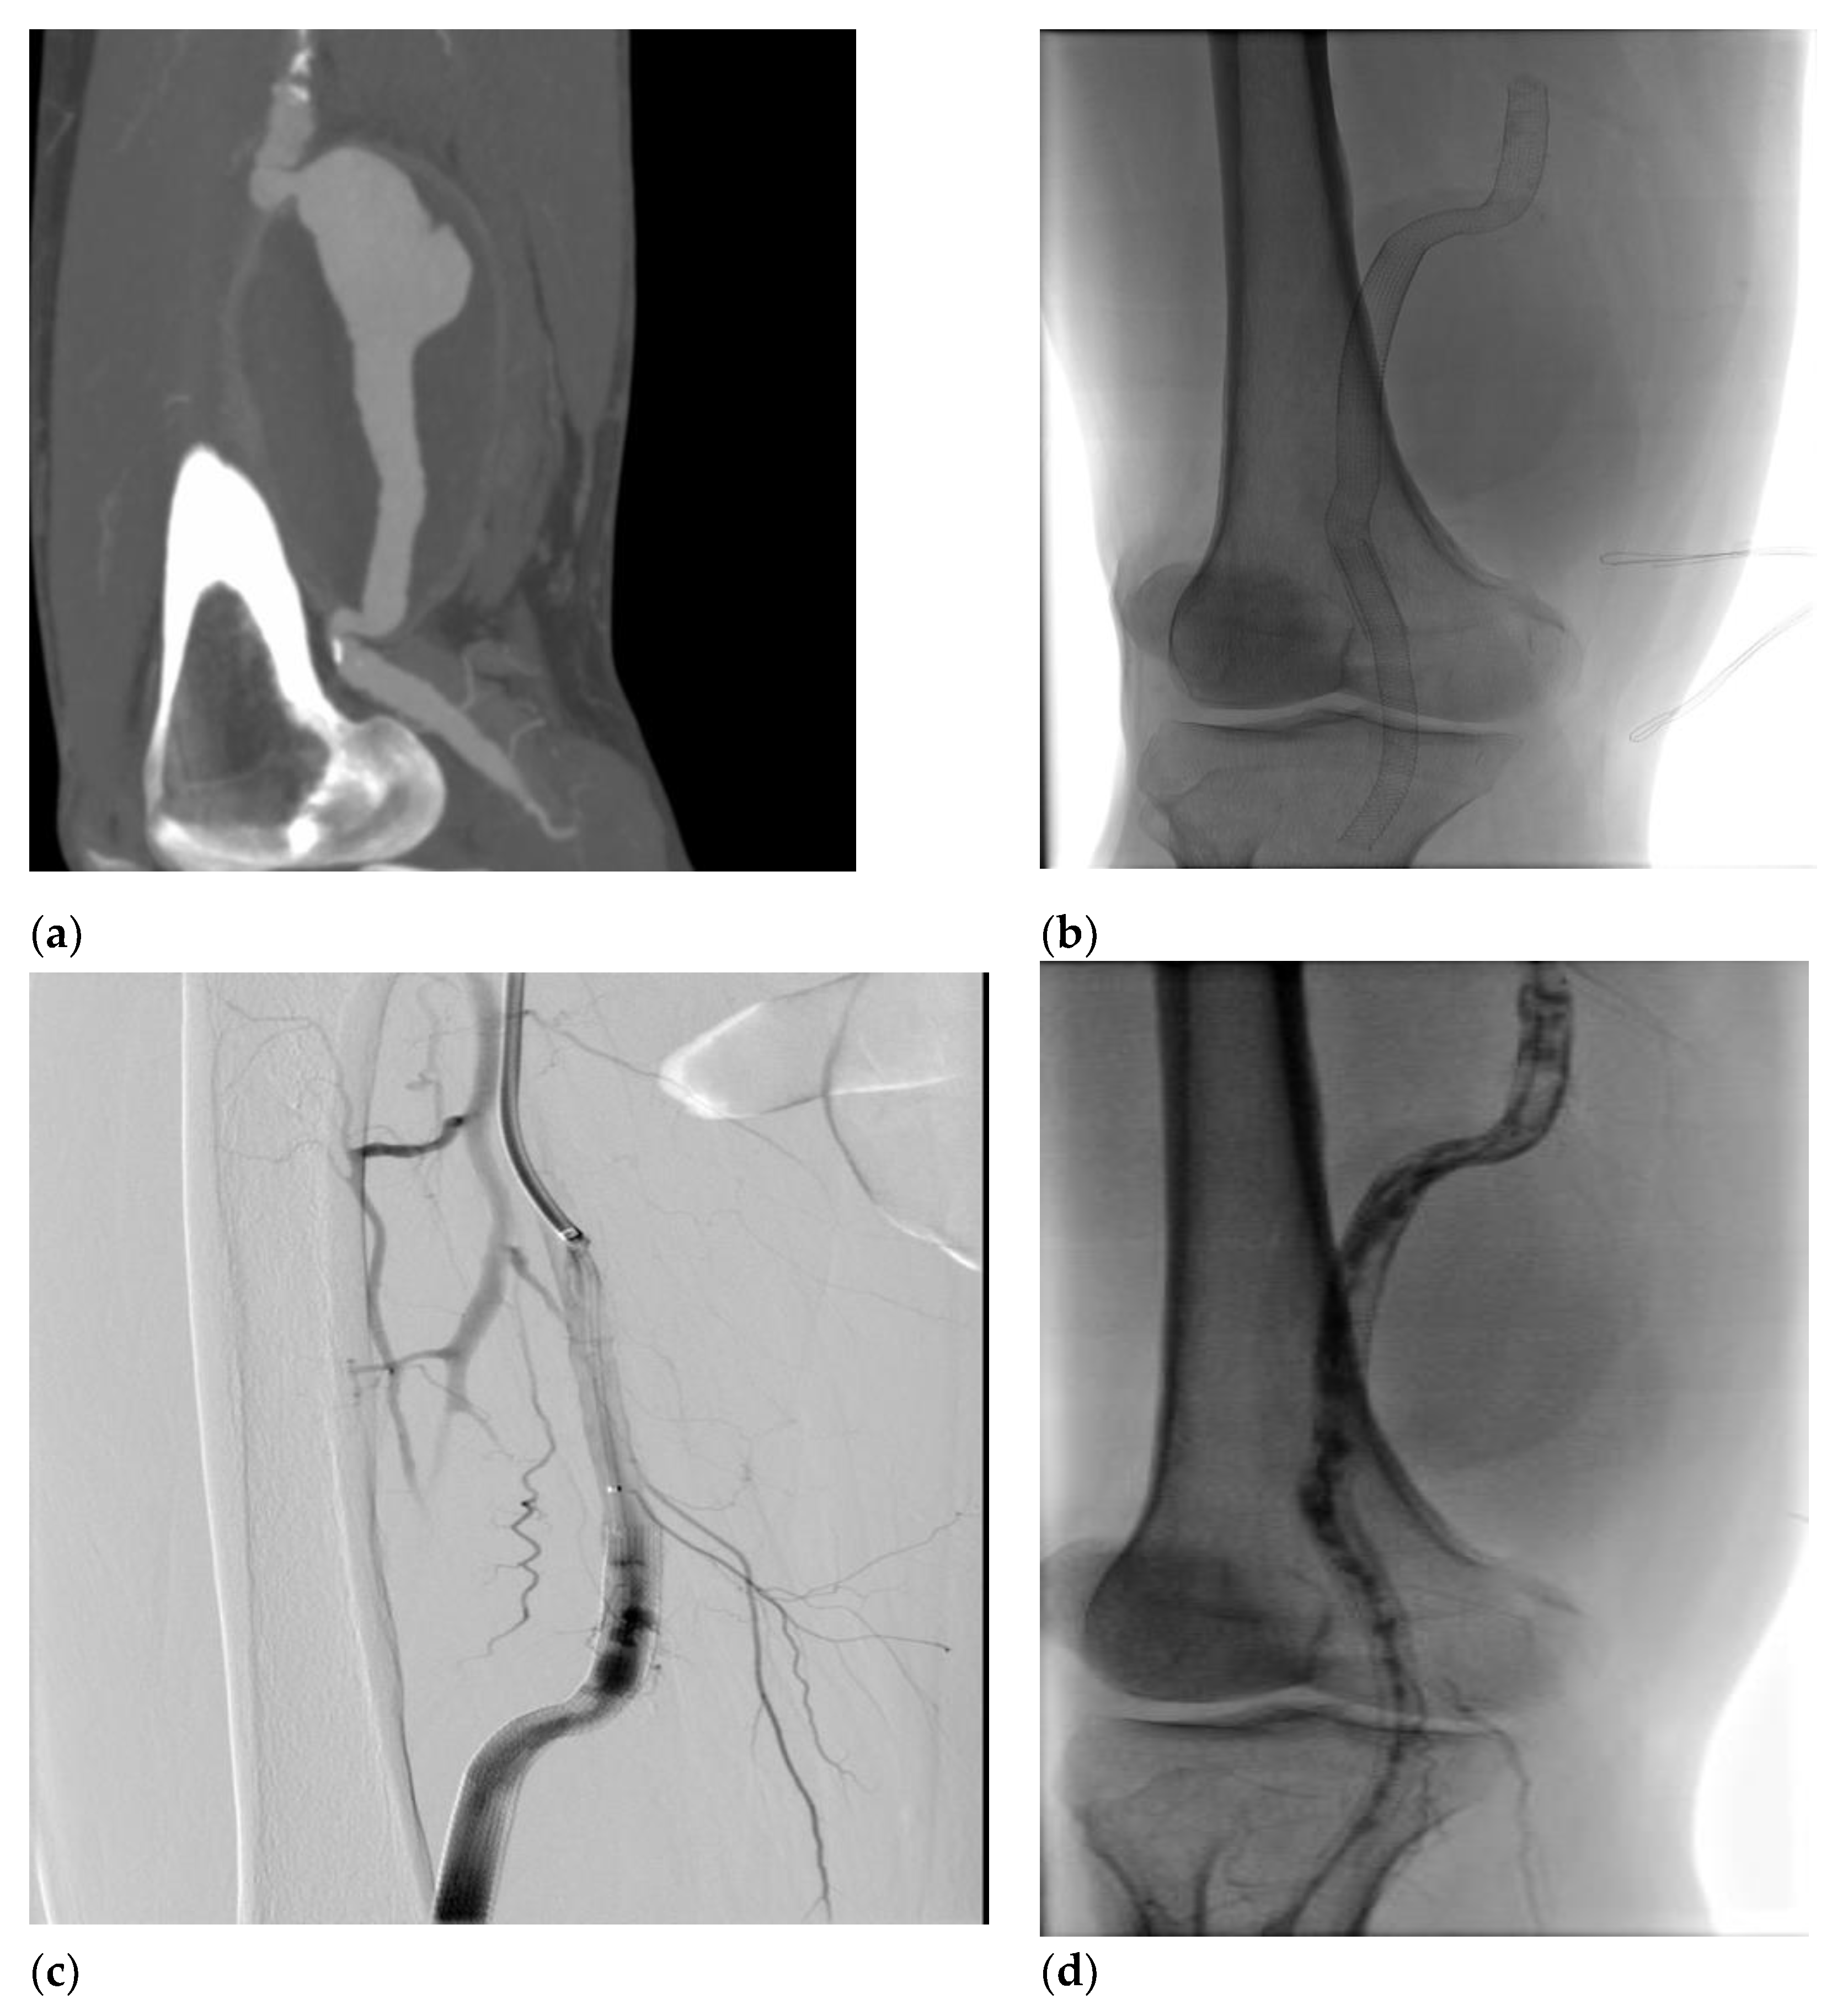

Figure 3. (a) (b) CTA images showing the popliteal abscess surrounding popliteal stent graft; (c) Femoropopliteal bypass with the biological bovine prosthesis. (d) Intraoperative stent graft explanted materials.

Deeply studying the ongoing popliteal status, we decided to perform a CTA that showed the presence of a peri-aneurysmatic fluid-corpuscular collection around the left popliteal artery (Figure 3). Moreover, we deemed the infective status necessary and worthy of further investigation. Microbiological exams revealed the presence of Staphylococcus aureus from blood and abscess material samples. Multidisciplinary teams with infective consultant collaboration believed in joint antibiotical therapy and open surgical treatment by abscess drainage and popliteal region reclaiming. After one week of antibiotic therapy, the patient underwent to femoropopliteal bypass using a biological pericardium bovine prosthesis with the final complete perviousness of the downstream vessels. The choice of biological prosthesis was because of the poor quality of patient’s saphenous veins. One-year follow-up revealed an ultrasound patency of bypass and tibiofemoral vessels and complete remission from infective status.